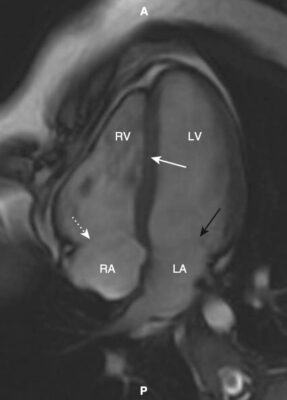

- Một trong những lợi ích của MRI là hình ảnh của nó có thể được hiển thị ở bất kỳ mặt phẳng nào. Bên cạnh các mặt phẳng cắt ngang (axial), đứng dọc (sagittal) và đứng bên (coronal, trán), có một số góc nhìn đặc hiệu thường được sử dụng trong MRI tim cho phép hình dung rõ nhất về tim. Chúng được gọi là trục dài cắt ngang (còn được gọi là mặt cắt bốn buồng), trục dài thẳng đứng, trục ngắn và mặt cắt ba buồng.

- Cấu trúc giải phẫu của tim trong các mặt phẳng cắt ngang, đứng dọc và trán giống như được thấy trên CT (Hình 16).

- Mặt cắt trục dài cắt ngang (bốn buồng) giống hình cắt ngang và được sử dụng tốt nhất để đánh giá vách ngăn và thành bên và đỉnh của tâm thất trái, thành tự do của tâm thất phải và kích thước của các buồng tim. Các van hai lá và van ba lá đặc biệt nhìn rõ ràng trong hình ảnh này (Hình 17).

- Trục dài đứng dọc giống như lát cắt đứng dọc và được sử dụng để đánh giá thành trước và thành dưới và đỉnh của tâm thất trái (Hình 18).

- Lát cắt trục ngắn mô tả tâm thất trái và phải để thực hiện các đo lường thể tích (Hình 19).

- Bởi vì hình ảnh MRI của tim đã được thu được với các thể tích ba chiều ở cả cuối tâm thu và cuối tâm trương, có thể thực hiện các đo lường khối lượng tâm thất, thể tích cuối tâm trương và thể tích cuối tâm thu dựa trên máy tính, và qua đó tính được thể tích nhát bóp và phân suất tống máu mà không cần can thiệp.

- Lát cắt ba buồng tương tự như lát cắt đứng bên và hiển thị gốc động mạch chủ và van động mạch chủ, đường ra thất trái, van hai lá, các thành trước vách và thành dưới bên của tâm thất trái (Hình 20).

- Tùy thuộc vào chuỗi xung MRI được sử dụng để thu được hình ảnh, máu có thể được mô tả là đen (thường sử dụng một xung gọi là chuỗi xung spin echo) và thường được sử dụng để đánh giá giải phẫu, hoặc sáng, nghĩa là màu trắng (thường sử dụng một chuỗi xung gọi là chuỗi xung echo gradient), và thường được sử dụng nhất để đánh giá chức năng (Hình 21).